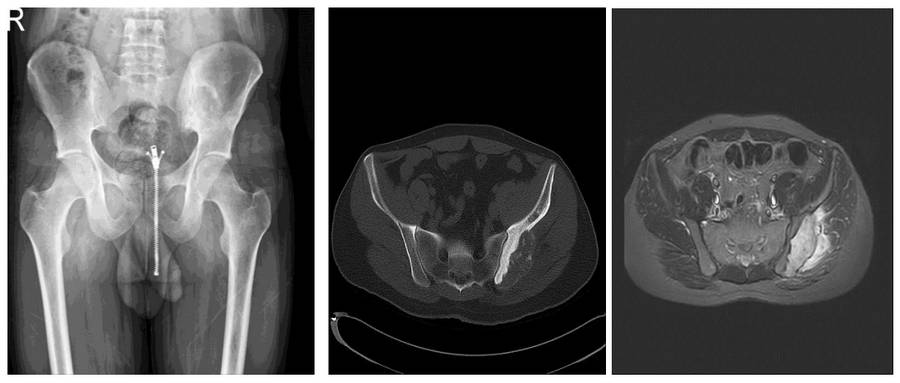

- Yapılan radyolojik tetkiklerde sol iliak kanat posteriorda kemik harabiyetine neden olan ve yumuşak doku komponenti bulunan kitle saptandı

Ameliyat Öncesi: Röntgen’de sol iliak kanat posteriorda düzensizlik, Tomografi’de kemik harabiyeti, MR’da eşlik eden yumuşak doku komponenti görülmekte